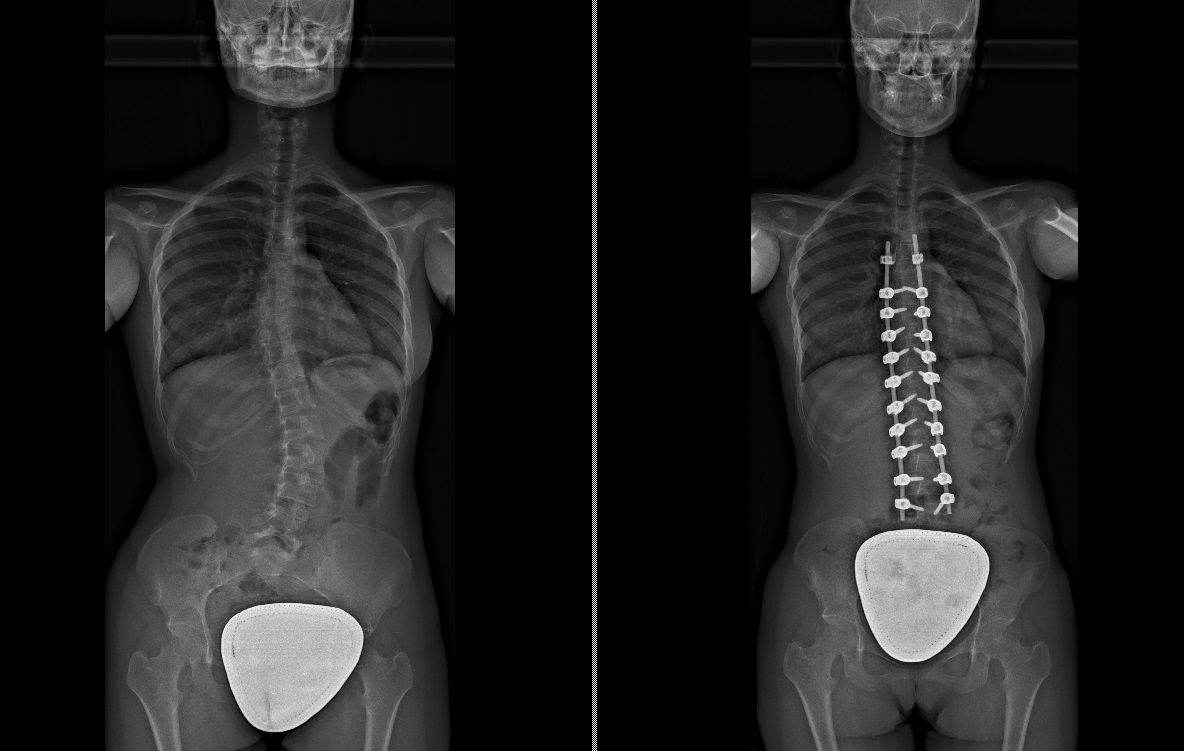

Foto e video